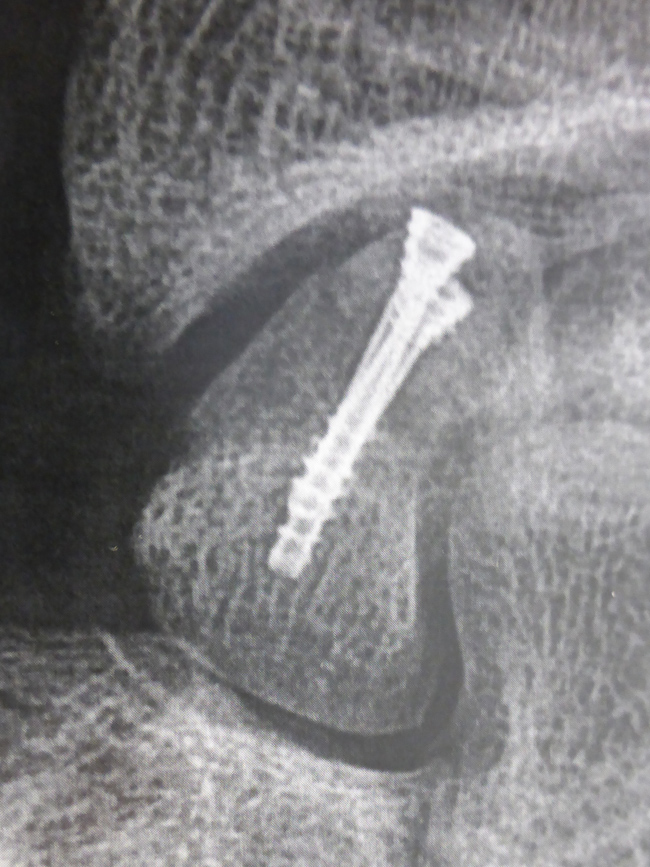

La vis est introduite à travers la peau par une très petite incision .

La vis est introduite par une toute petite incision. La position de la vis est contrôlée par des radiographies pendant l’intervention.